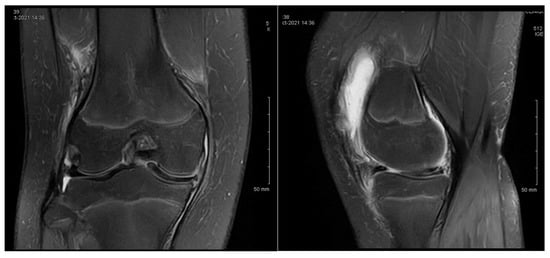

3.1. Case 1—P.E.

3.2. Case 2—S.C.S.

3.3. Case 3—G.L.